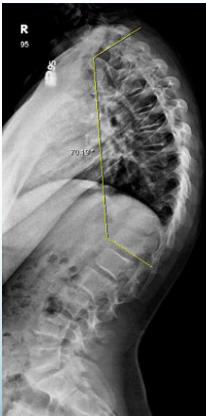

Kyphosis

Less common than scoliosis

- Kyphosis: Abnormal thoracic curve >40°

- KYPHOSIS: Dorsal curvature of the spine >40°

Definition

Backward angulation above 40 degrees